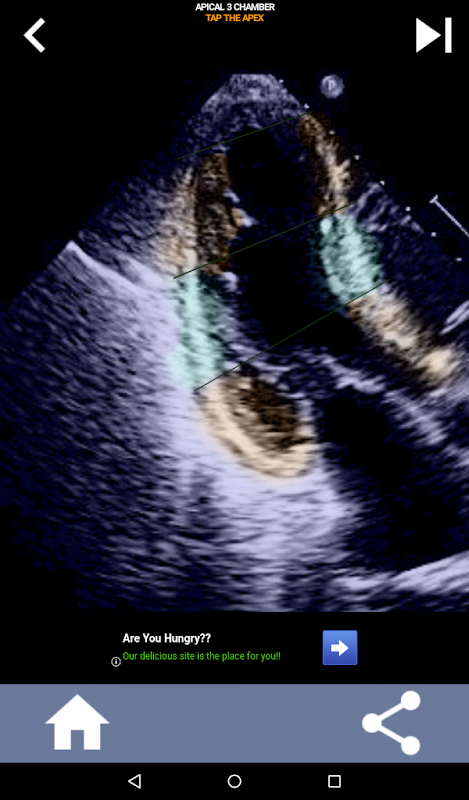

AHA 심장 세그먼트 학습을 위한 퀴즈 기반의 시각적 접근 방식: 심초음파

AHA(미국 심장 협회) 심장 세그먼트를 이해하는 것은 심장 초음파 기사가 보고서를 작성하는 심장 전문의와 효과적으로 의사 소통하는 데 가장 중요합니다. 특정 해부학적 부위와 해당 부분을 알면 소노그래퍼는 모든 이상 또는 발견 사항을 정확하게 설명하고 전달할 수 있으므로 두 전문가 간의 명확하고 간결한 커뮤니케이션이 보장됩니다.

이러한 이해는 심장 전문의가 문제의 정확한 위치를 확인하려고 하거나 당직 의사가 특정 영역 내에서 문제를 식별하여 소노그래퍼가 중하벽과 같은 해당 부분을 정확하게 표시하도록 유도할 때 특히 중요합니다. 따라서 AHA 심장 부분을 포괄적으로 파악하는 것이 필수 기술입니다.

이 앱은 실제 에코 이미지를 사용하여 여러분의 지식을 테스트할 것입니다. 저는 종종 이것이 최고의 교육 방법이라고 생각합니다.